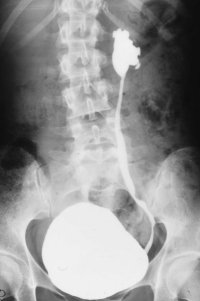

Neben der Anamnese, körperlicher Untersuchung, Messung des Blutdruckes sowie der Laboruntersuchungen: Urinstatus, Serumkreatinin und -Elektroylte ist die Sonographie zur Feststellung einer einseitig kleinen Niere zielführend (Abbildung 10a). Zur Diagnostik zählt fernerhin die NFZG (Abbildung 10b) bzw. Computertomographie.

Die Abbildungen zeigen die Anwendung von Sonographie und Miktionszysturethrogramm bei einer kleinen stummen Niere (Abbildung 13, 14).